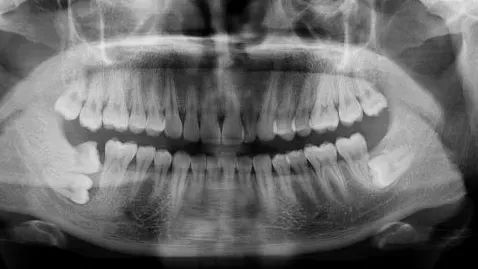

▲七号牙近中生长 + 阻生智齿。